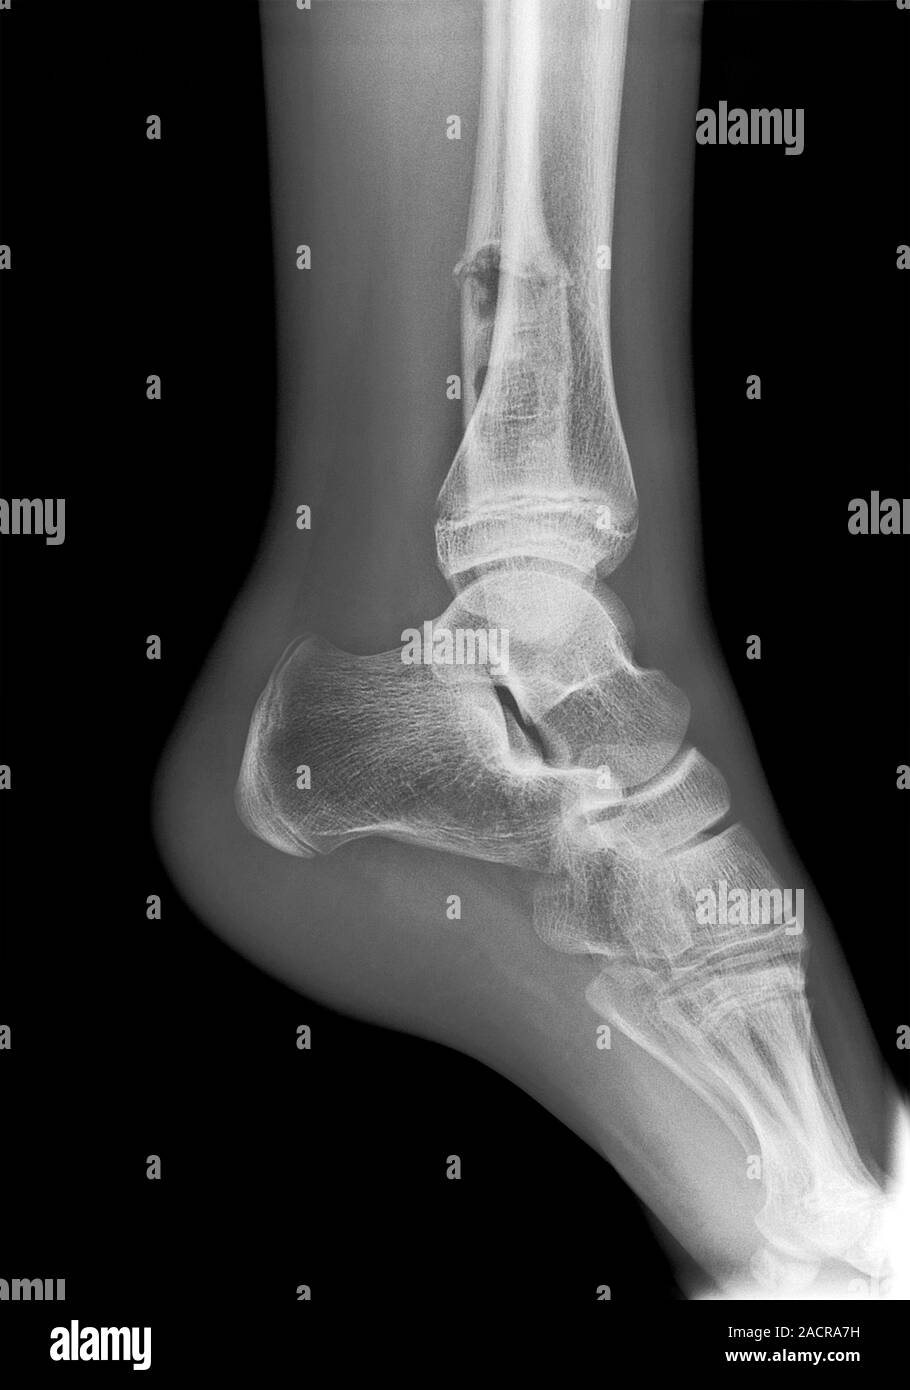

Ankle Fracture X Ray Photos . The tibia (shinbone), the fibula (outer bone of the lower leg),. ankle fractures account for ~10% of fractures encountered in trauma, preceded only in incidence by proximal femoral fractures in the. Ankle fractures are usually bony injuries involving the distal tibia (medial malleolus) or distal fibula (lateral malleolus). Occasionally the articular surface of the talus can be injured. a broken ankle is a fracture or multiple fractures of one or more of three bones in the ankle joint: Medial malleolus fracture and lateral malleolus.